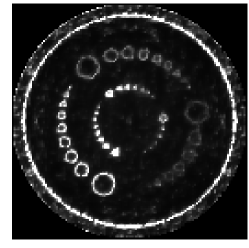

The process of HO classification is outlined schematically in Fig. 2. Note that noise in the images introduces statistical variability in the outcome of the test statistic for each hypothesis. The task of the HO can then be interpreted as the construction of a linear test statistic which has maximally separated statistical distributions under the two hypotheses.

The reconstruction algorithm used was the FBP algorithm discussed in section 2. Projection data for the reference case was acquired over a full rotation at 1024 evenly spaced angles with 256 detector elements. The reconstruction was performed onto a pixel image grid with pixels roughly twice the size of a single detector element. The images were then cropped to a central pixel ROI, which was then displayed at magnification. Black and white lines were then superimposed on the image in order to aid the observers in localizing the signal at the center of the ROI. The reference images for the human and model observer study were reconstructed without regularization, i.e. with only the ramp kernel used for filtration. The ratio of the source-to-detector distance to the source’s radius of rotation was . The reference reconstructed signal is shown on the top left of Fig. 1. Visible artifacts in the reconstructed signal are a result of the discretization in the sinogram and image domains and the small size of the signal. This small signal size is desirable in this case because we can then expect greater variability in observer performance with respect to the reconstruction algorithm with the given noise model. The corresponding Hotelling template is pictured on the top right of Fig. 1.

As mentioned in Section 2, regularization can be performed in fan-beam FBP by applying a multiplicative apodization window to the ramp kernel in the Fourier domain. A case of heavy regularization is considered here, wherein a Hanning window with cutoff frequency equal to of the Nyquist frequency is used. For this case, we expect a drop in HO SNR relative to the reference (unmodified ramp kernel) case since this multiplicative window will place high-frequency components of the weighted projection data in the null-space of the reconstruction operator. The mean reconstructed signal and Hotelling template for the regularized study are shown in the middle row of Fig. 1.

Next, we considered the case of reconstruction onto pixels which are a factor of four larger than in the reference case, i.e. approximately eight detector bin widths square. Here, the expected loss in HO SNR arises from the fact that the reconstruction matrix has a more significant null-space due to the lower number of output image pixels relative to the number of input data elements. In other words, the matrix is now farther from being square, transforming an -element data vector to an -element image array where . The mean reconstructed signal and Hotelling template for the study involving larger pixels is shown in the bottom row of Fig. 1. Example pairs of images used in the regularization and large pixel studies are shown in the middle and bottom of Fig. 3.